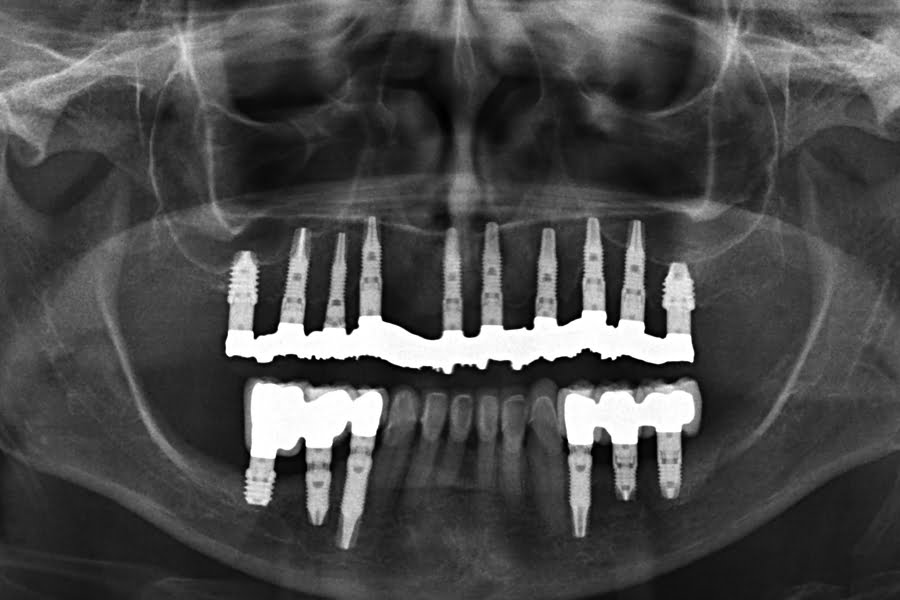

Quatro dos seis implantes foram de 5,5 mm de comprimento por 5 mm de diâmetro, um implante foi de 6,5 mm de comprimento por 3,75 mm de diâmetro e o último implante foi de 6,5 mm de comprimento por 5 mm de diâmetro (figura 2).

As seguintes imagens apresentam um dos casos incluídos no estudo (figura 03 – 15).